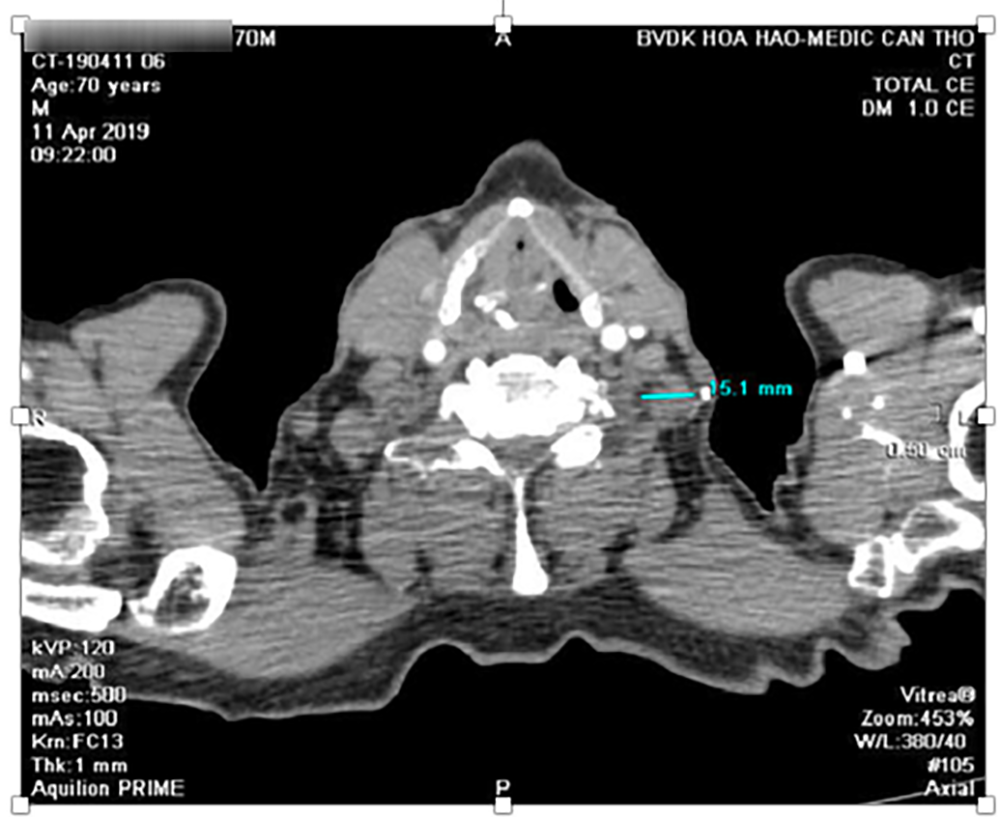

Msct toàn thân có tiêm thuốc cản quang

Hạch 14mm vùng thượng đòn trái